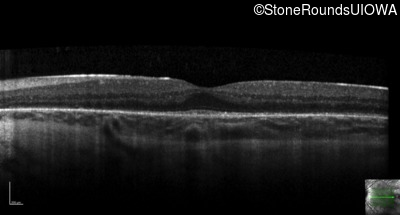

Optical Coherence Tomography - Right - 20/20 -3

Exemplar / OCT Stack

OCT Stack